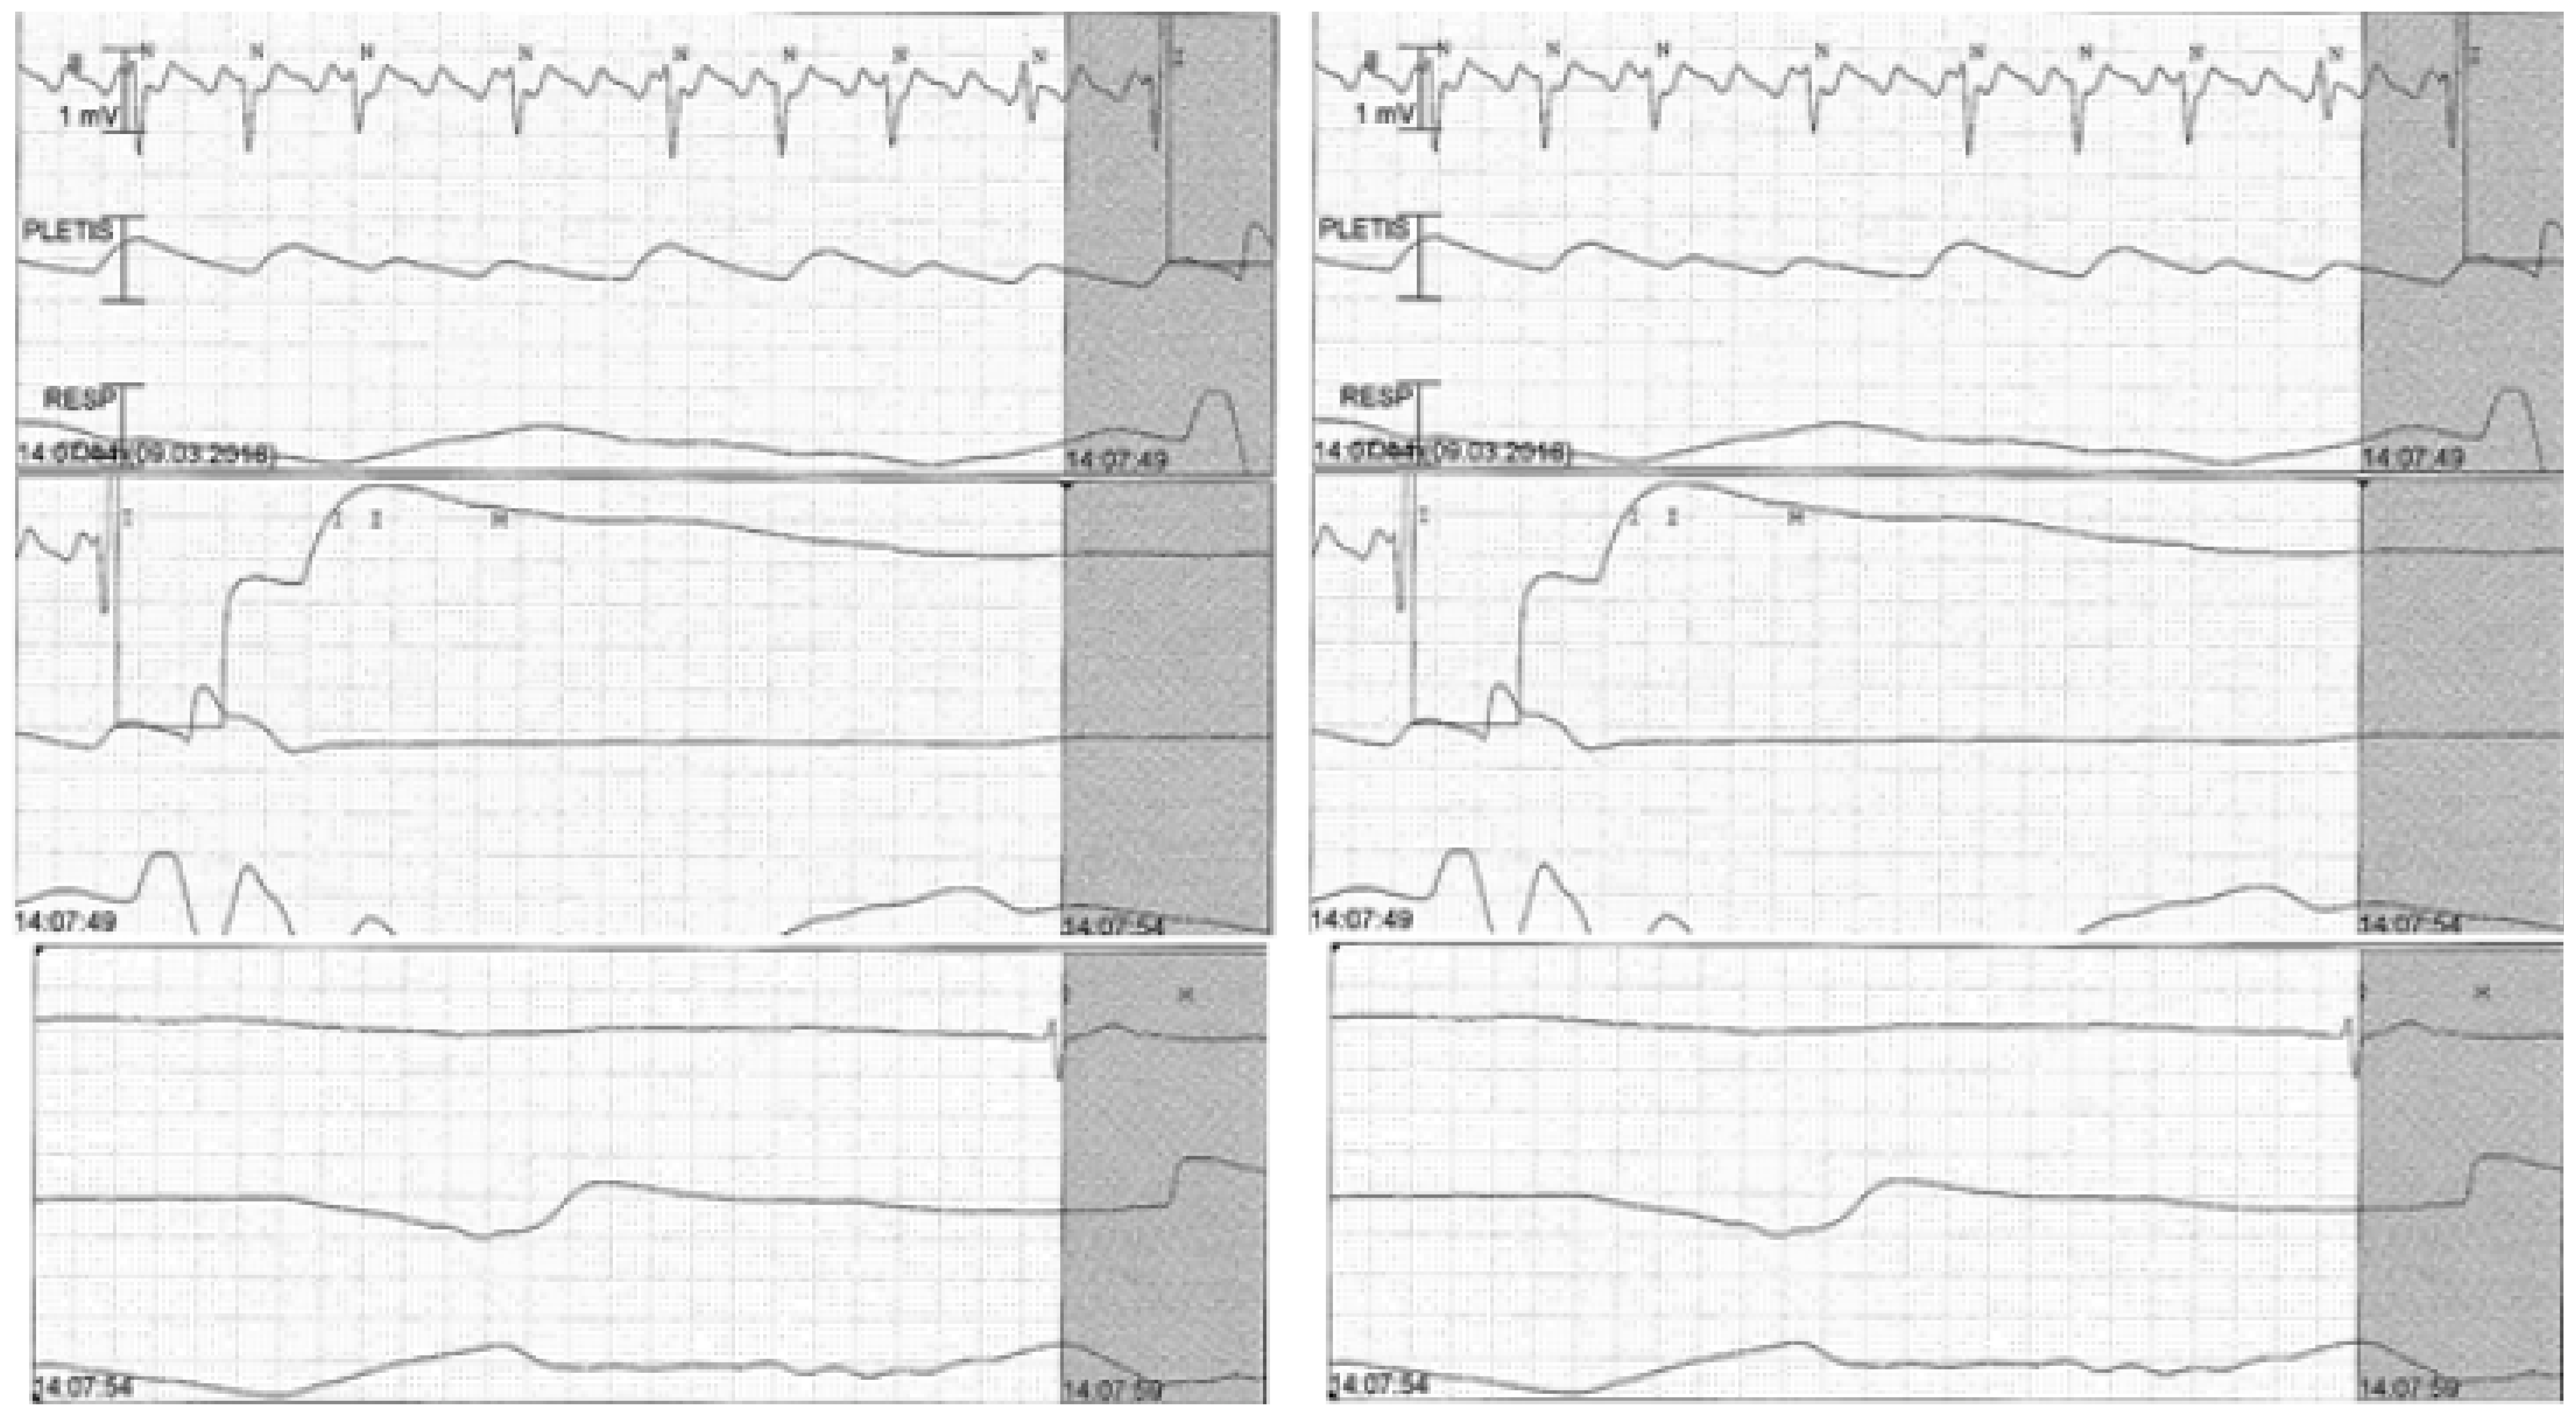

Transthoracic echocardiography (TTE) revealed mild left ventricular hypertrophy with normal systolic function. We decided to schedule the patient for electric cardioversion and we started oral anticoagulation (rivaroxaban 20 mg). After the first electric shock, there was a sinus arrest lasting 15 seconds, without ventricular escape rhythm (Figure 2).

Figure 2.

ECG monitoring showing sinus arrest (15 seconds) after electric cardioversion.